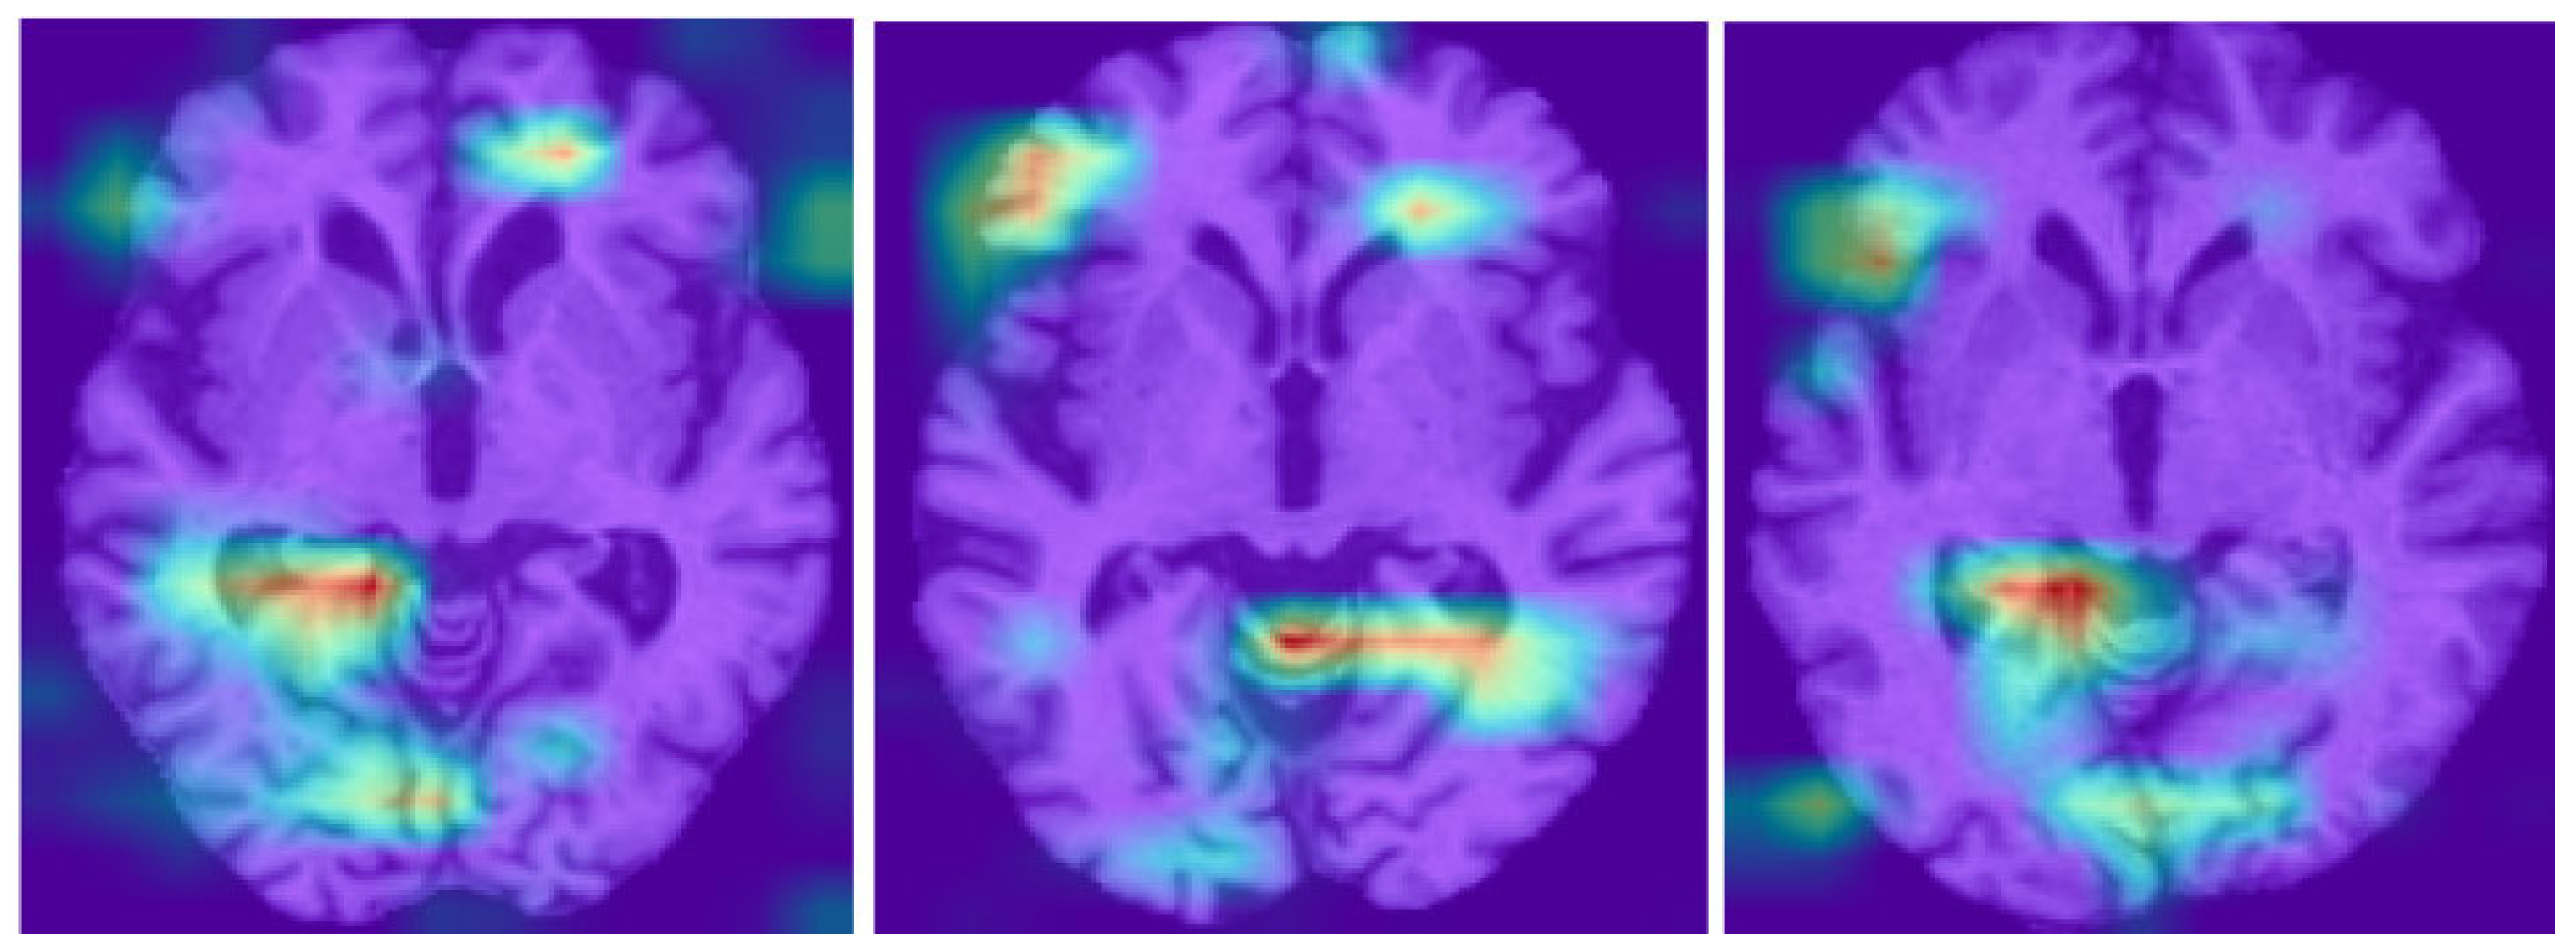

4.2. Grad-CAM Visualization

| Grad-CAM | Gradient-weighted class activation mapping |